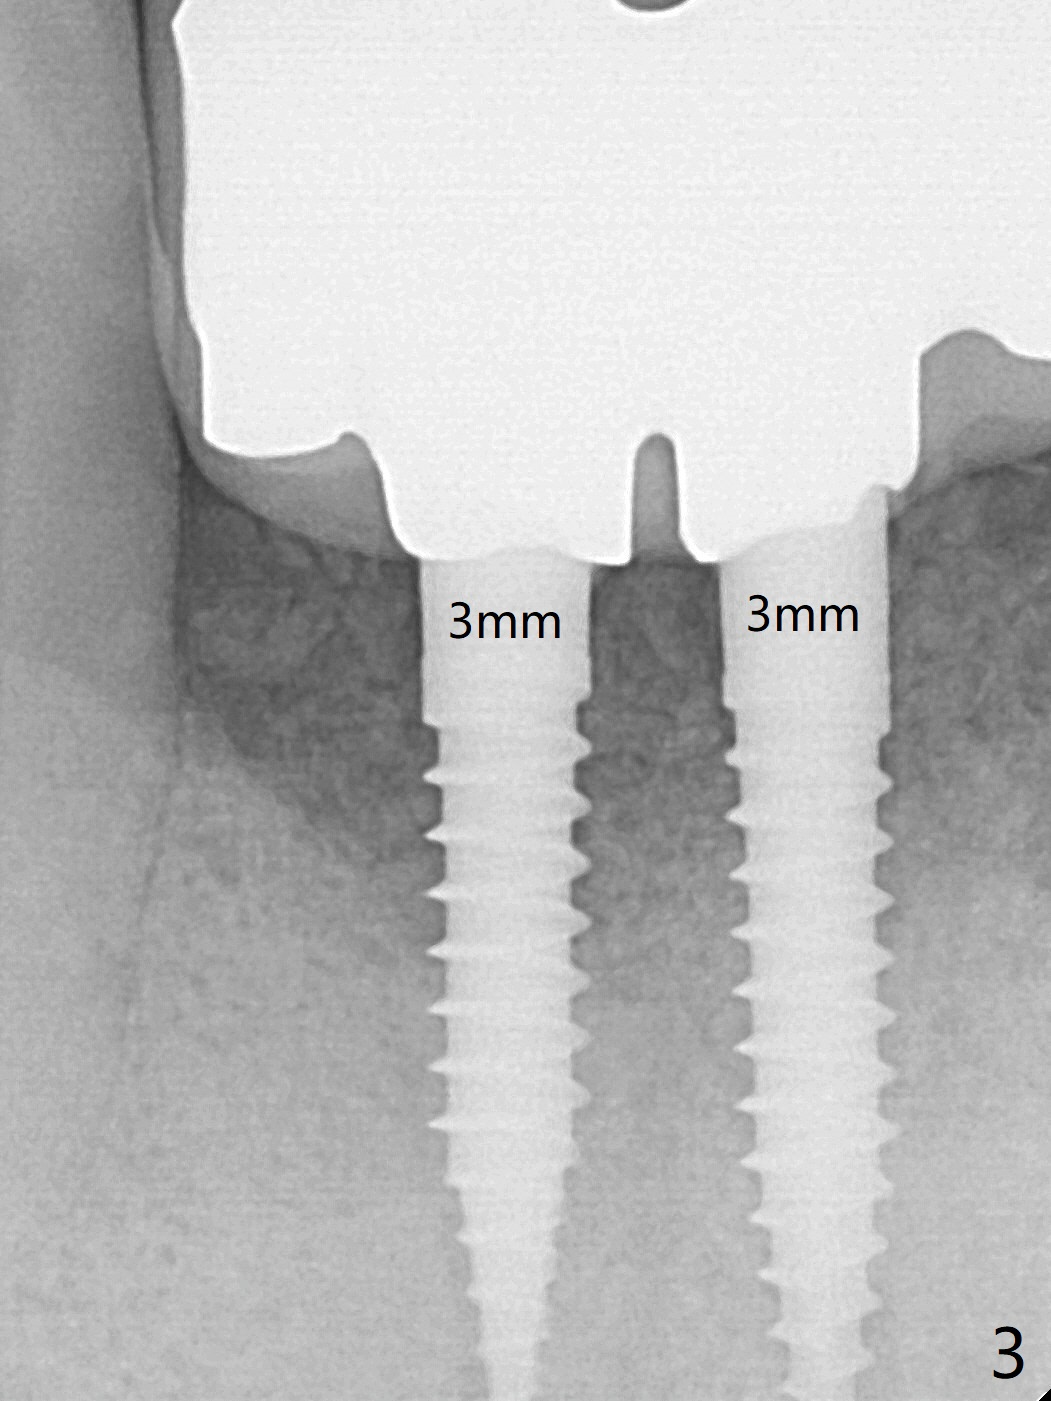

The fenetration found buccal to #25 two months post cementation persists, although asymptomatic, 4 months post cementation. Blood is drawn for PRF. In fact the implants at #24 and 25 are exposed buccal; there is limited amount of the buccal bone (Fig.1 *). After granulation tissue removal, Titanium brush is used to clean the implant threads. Allograft and Osteogen are mixed with PRF liquid to form gel, which is placed over the exposed implant threads. The bone graft is covered with a piece of PRF membrane and a piece of collagen membrane (Fig.2 C). Immediately postop PA (Fig.3) and CBCT (Fig.4) show that the implants have sufficient clearance between them. The implant thread exposure is most likely due to failure to place the implants deep enough and the implants are slightly large relative to the ridge (Fig.5-8). If the bone graft does not heal, new type of 1-piece implants (Fig.9,10 (green) smaller in diameter, 2 or 2.5 mm ) with longer abutment (pink) will be placed subcrestal buccal with guide.